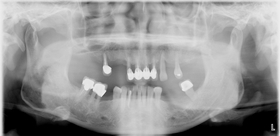

全口植牙重建

治療前X光片,多處缺牙及嚴重牙周破壞。